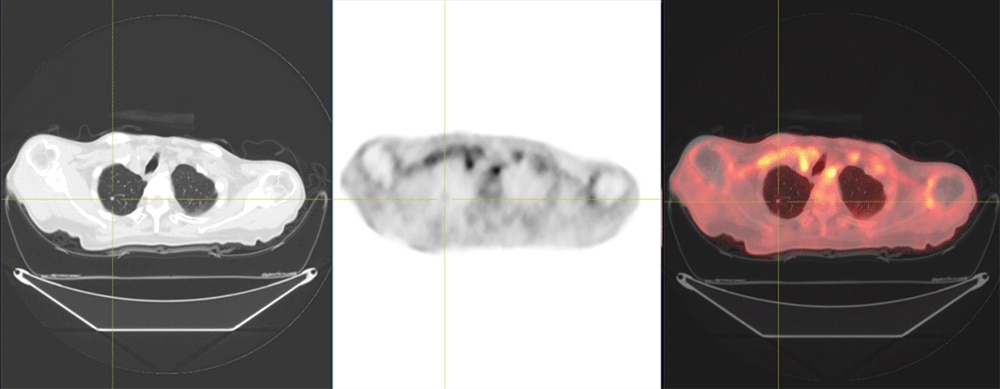

70代 男性 肺がん:術後脳転移に対する放射線治療後の全身検索目的でFDG-PET検査施行

約4mmの肺転移(SUVmax=0.84)

約9mmの肺転移(SUVmax=2.08)